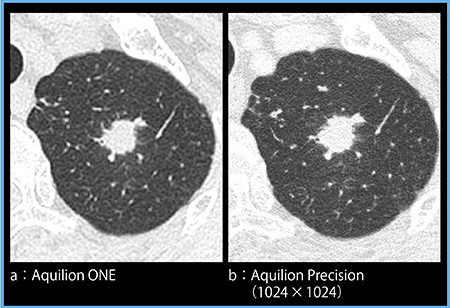

症例2は,当院にて近い間隔で撮影したAquilion ONE(図2 a)とAquilion Precision(1024×1024マトリックス)の画像(図2 b)である。Aquilion Precisionでは,辺縁不整であることが一目瞭然であり,直感的かつ容易に診断のための所見を取ることができる。

図2 症例2:肺腺癌(solid nodule)